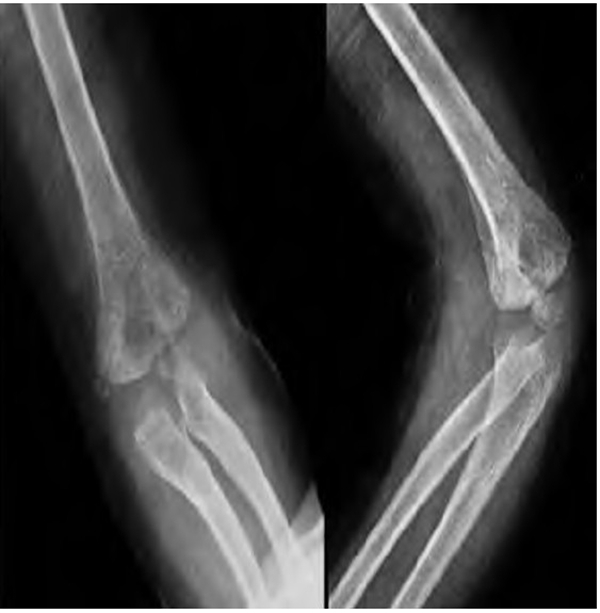

术后予止血、消肿、口服甲钴胺营养神经及抗感染对症治疗,定期创口换药。术后复查DR片提示骨折断端对位对线可,内固定位置良好,桡骨头复位良好,肘关节位置良好(图2)。术后7周拔除克氏针进行功能训练(图3)。术后3个月复查DR片提示骨折断端骨折线已消失,可见较多骨痂影(图4)。随访3年10个月,患儿无肘内、外翻畸形,无肘关节及腕关节活动受限(图5),肘关节 Mackay功能评分为优。

图4 术后3个 月 DR片 示骨折断端对位对线可,骨折线已消失,可见骨痂影